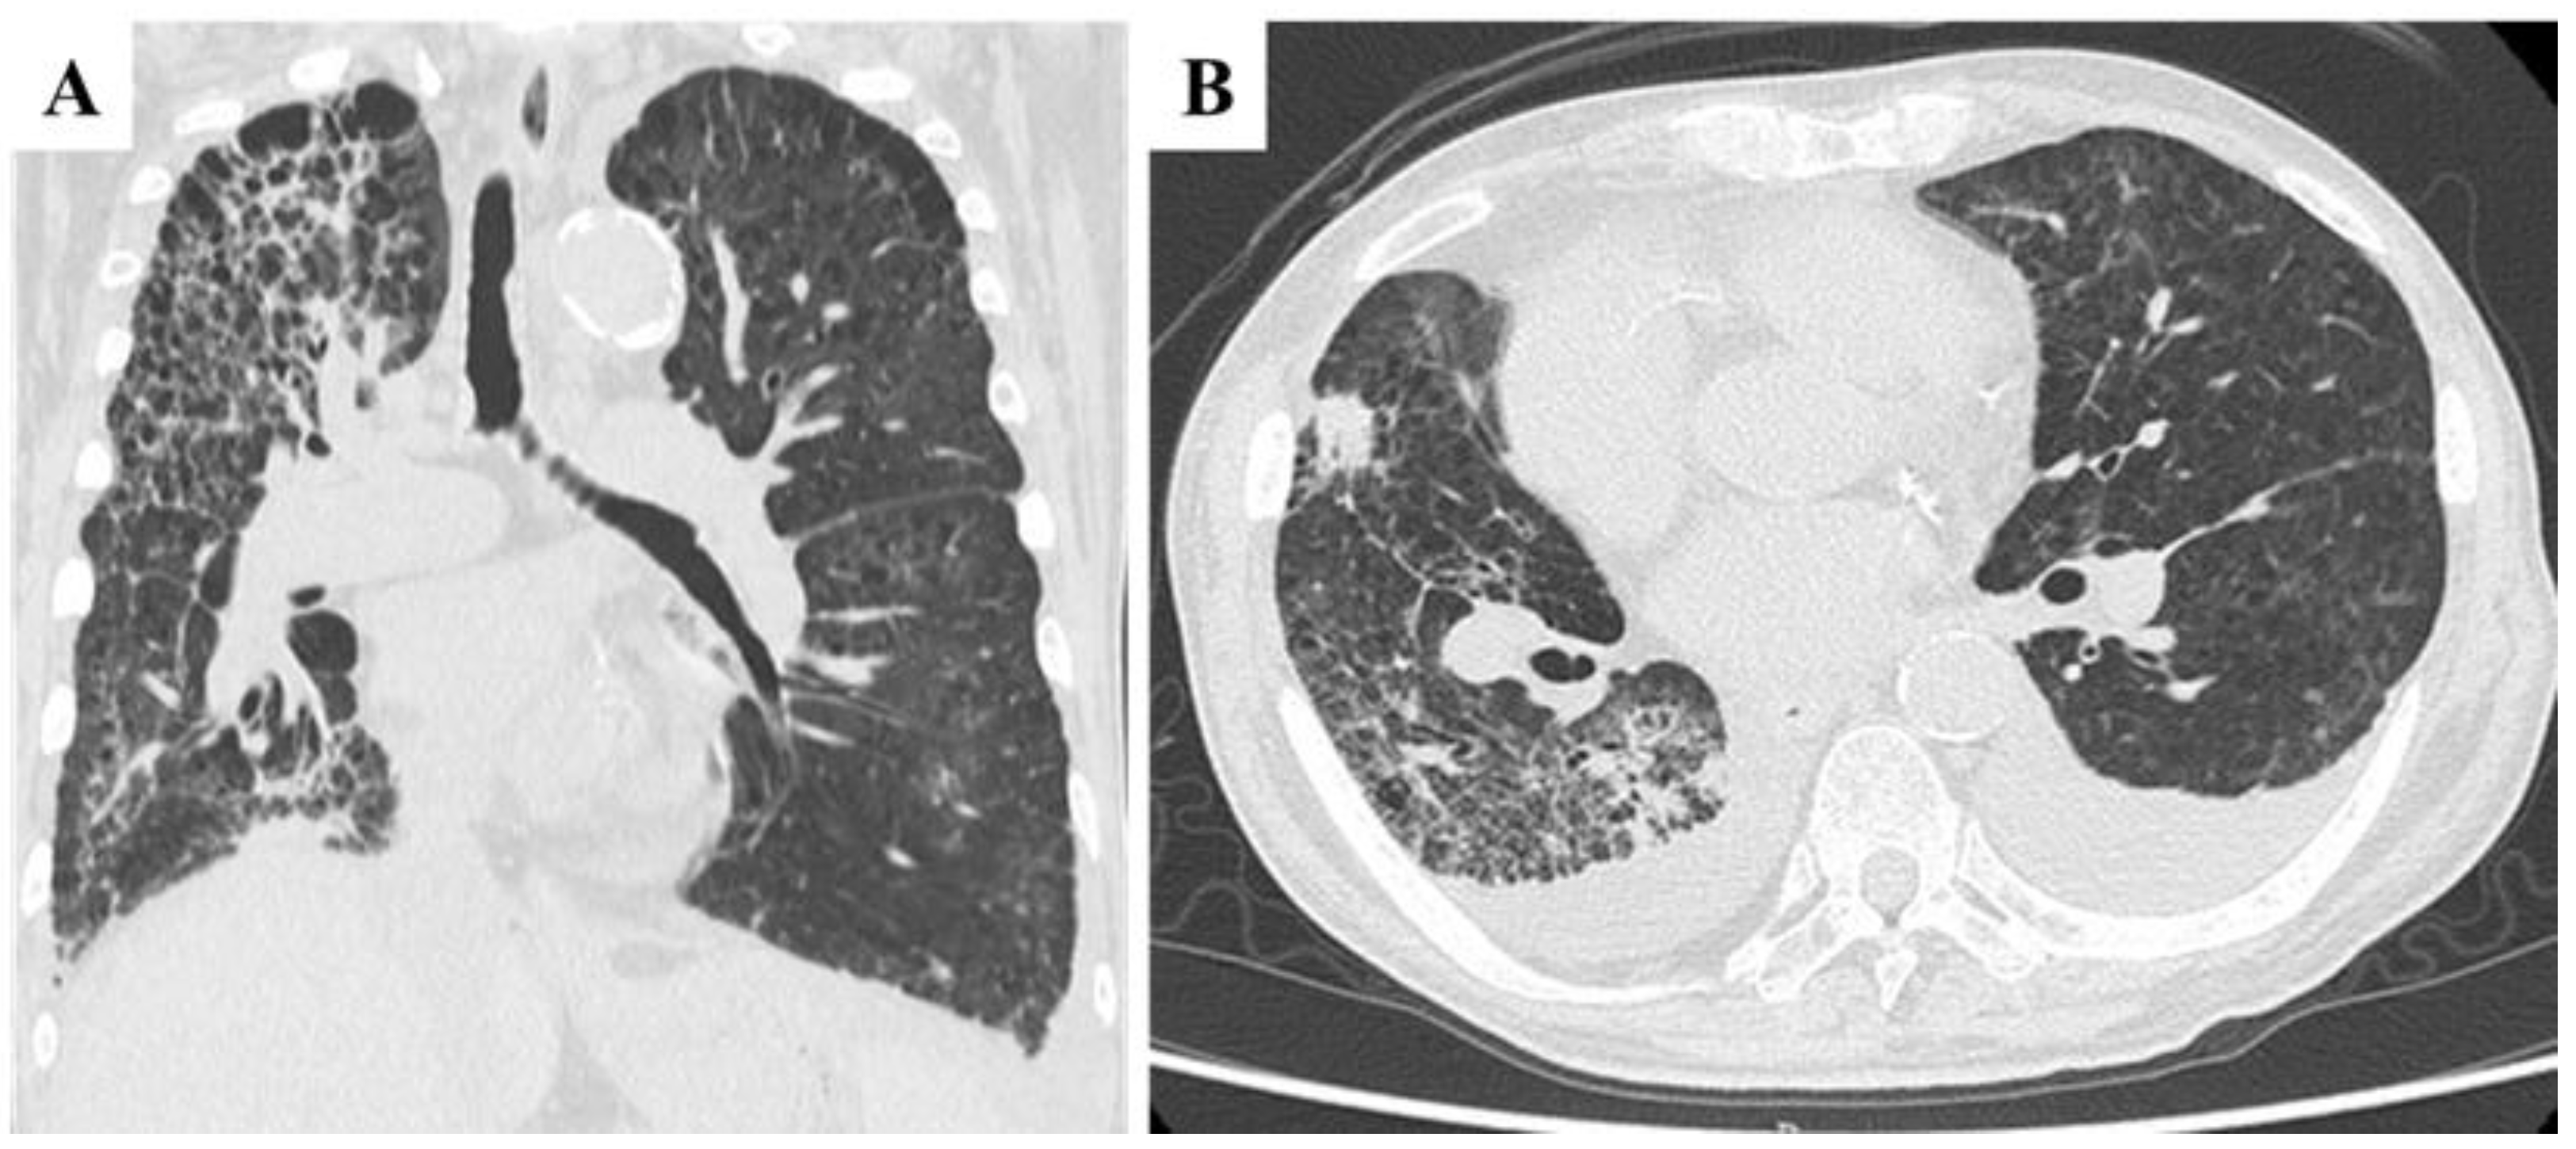

A 70-year-old Japanese male with a history of smoking and alcohol consumption underwent an annual health check-up, during which a fecal occult blood test returned positive for the first time. Subsequent investigations led to a diagnosis of transverse colon cancer with peritoneal metastases. Contrast-enhanced computed tomography (CECT) revealed an irregular mass in the transverse colon near the hepatic flexure, along with multiple peritoneal nodules primarily localized to the greater omentum [Figure 1A]. Chest CT revealed multiple blebs in both lung apices and a reticular pattern in the right lung [Figure 1B]. Despite peritoneal dissemination, no hematogenous or lymphatic metastases were evident at this stage.

Figure 1. Pretreatment findings from abdominal contrast-enhanced CT and chest CT. A: Coronal section view showing a tumor in the transverse colon near the hepatic flexure (arrow) and a peritoneal metastatic nodule located just caudal to the primary tumor (arrowhead). Several additional peritoneal metastatic nodules were observed along the greater omentum (not shown). B: Chest CT revealed multiple blebs in both lung apices, along with a reticular pattern in the right lung lobes.

The initial treatment regimen consisted of capecitabine, oxaliplatin, and cetuximab. However, after three cycles, imaging indicated disease progression, with an increase in peritoneal disseminated nodules. Chemotherapy was subsequently modified to capecitabine plus irinotecan and bevacizumab. Despite eight cycles, significant ascites accumulation and mesenteric shortening were observed [Figure 2A]. At this stage, the tumor remained an irregular mass without evidence of hematogenous metastases, although concerns about rapid disease progression persisted. Compared with pretreatment findings, chest CT revealed no significant worsening of reticular or interstitial shadows [Figure 2B].

Figure 2. Abdominal contrast-enhanced CT (CECT) and chest CT findings after eight cycles of chemotherapy with capecitabine, irinotecan, and bevacizumab, following resistance to capecitabine, oxaliplatin, and cetuximab. A: Coronal section view showing a large volume of ascitic fluid and mesenteric shortening. The tumor in the transverse colon appeared as an irregular mass (arrow). B: Chest CT revealed no significant progression of reticular or interstitial shadows compared with pretreatment findings.